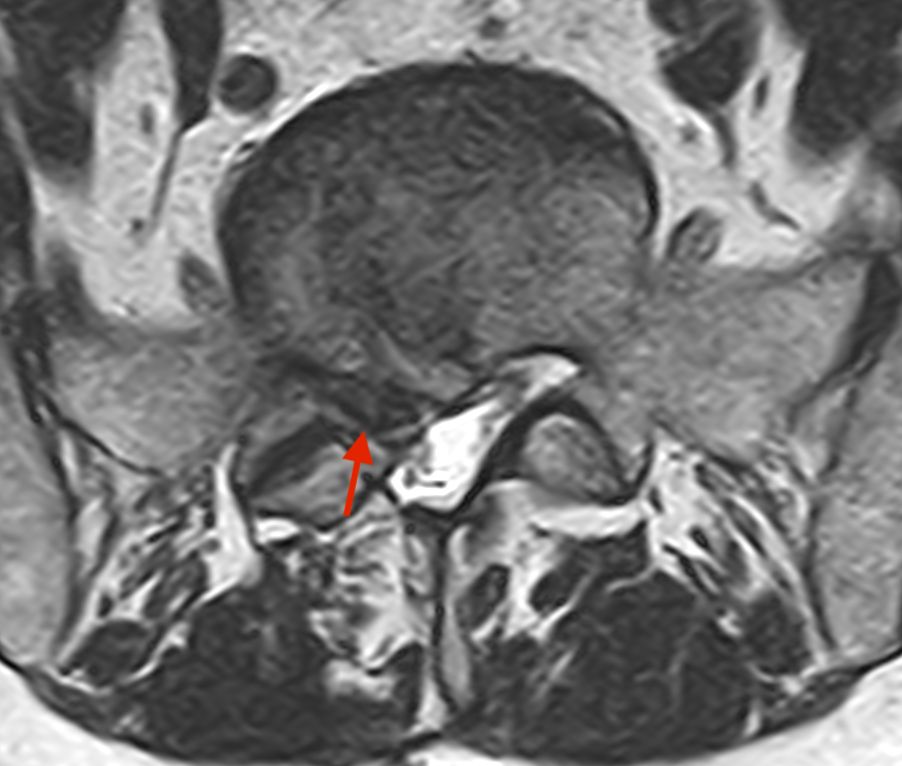

Dopo la laurea e la specializzazione in Neurochirurgia con lode presso il Policlinico Agostino Gemelli, ho dedicato la mia formazione esclusivamente alla cura delle malattie della colonna vertebrale e del midollo spinale, come ernie del disco, stenosi del canale vertebrale, spondilolistesi, metastasi vertebrali e tumori del midollo spinale, attraverso esperienze presso centri di riferimento italiani ed internazionali e a numerosi corsi e master di II livello.

Queste patologie si manifestano con sintomi neurologici (ad esempio: dolore o perdita di forza ad un arto, formicolii, rigidità o perdita di coordinazione alle mani o durante la marcia) oppure con sintomi meccanici (ad esempio: mal di schiena prevalente durante il movimento). Una valutazione specialistica deve mirare a correlare i sintomi clinici con le alterazioni presenti alle immagini radiologiche, ed a guidare il paziente attraverso il percorso di cura, finalizzato al recupero della sua ottimale qualità di vita.

• ernia del disco cervicale, toracica e lombare;

• stenosi del canale vertebrale cervicale e lombare;

• mielopatia cervicale spondilogena;

• spondilolistesi cervicale e lombare;

• scoliosi degenerativa dell’adulto;

• cifosi degenerativa dell'adulto;

• deformità degenerative dell'adulto.